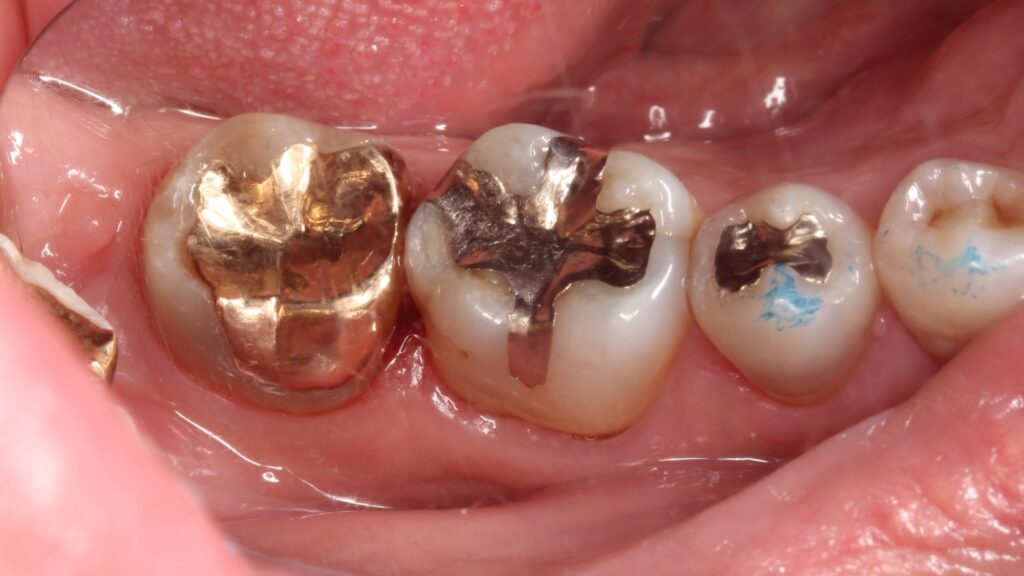

長年使っていた銀歯がある日突然外れることがあります。今回は、そんな主訴の患者様の症例です。

麻酔下で感染歯質を取り除き、裏装を兼ねてセメントを充填し痛みが出ないか経過観察を行った。

その後、生活歯であること、隣接歯をはじめ全顎的に咬耗があり、咬筋測定の結果、咬合力が強いことも考慮しゴールドアンレーを選択しました。